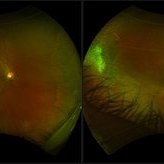

Sickle cell retinopathy (Proliferative) (2 files)

Sickle cell retinopathy (Proliferative) (2 files)

Dark without pressure (3 files)

Dark without pressure (3 files)

Proliferative Sickle Cell Retinopathy (Stage3) (10 files)

Proliferative Sickle Cell Retinopathy (Stage3) (10 files)

Sickle Cell Retinopathy (11 files)

Sickle Cell Retinopathy (11 files)